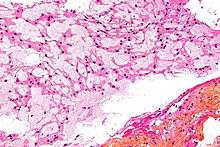

There are three histological variants of chordoma: classical (or "conventional"),[7] chondroid and dedifferentiated.

- The histological appearance of classical chordoma is of a lobulated tumor composed of groups of cells separated by fibrous septa. The cells have small round nuclei and abundant vacuolated cytoplasm, sometimes described as physaliferous (having bubbles or vacuoles).